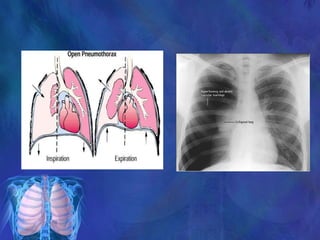

Open Pneumothorax

(Sucking Chest Wound)

Open chest wall injury

Stab wounds usually self-sealing

Extensive damage

Air passes through opening into

the pleural space and remains

outside of lung

Large open defect in chest wall

(>3 cm diameter) with

equilibration between

intrathoracic and atmospheric

pressure

MECHANISM

Opening of chest wall exceeds two third of the

diameter of the trachea

with each inspiratory cycle air is drawn through

the defect rather than through the trachea

Accumulation of air in hemithorax rather than in the

lung

Leading to profound hypoventilation on the affected

side and hypoxia

If there is valvular effect increasing air

accumulation in the pleural cavity results in a

tension pneumothorax